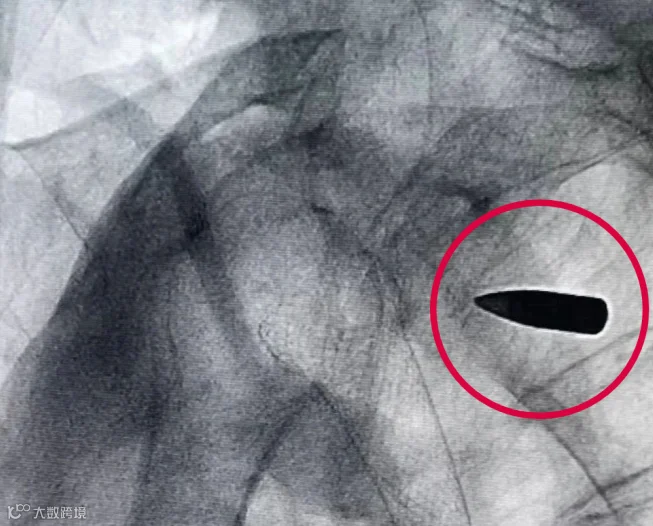

CT拍出来

医生们都吓了一跳

罗锦文的右肩里

竟然有一颗子弹

这颗“长”在他身体里70多年的子弹

是对那段历史的见证

考虑到这枚子弹对日常生活影响不大

经医院和家属商议

决定保持原状

不进行取出